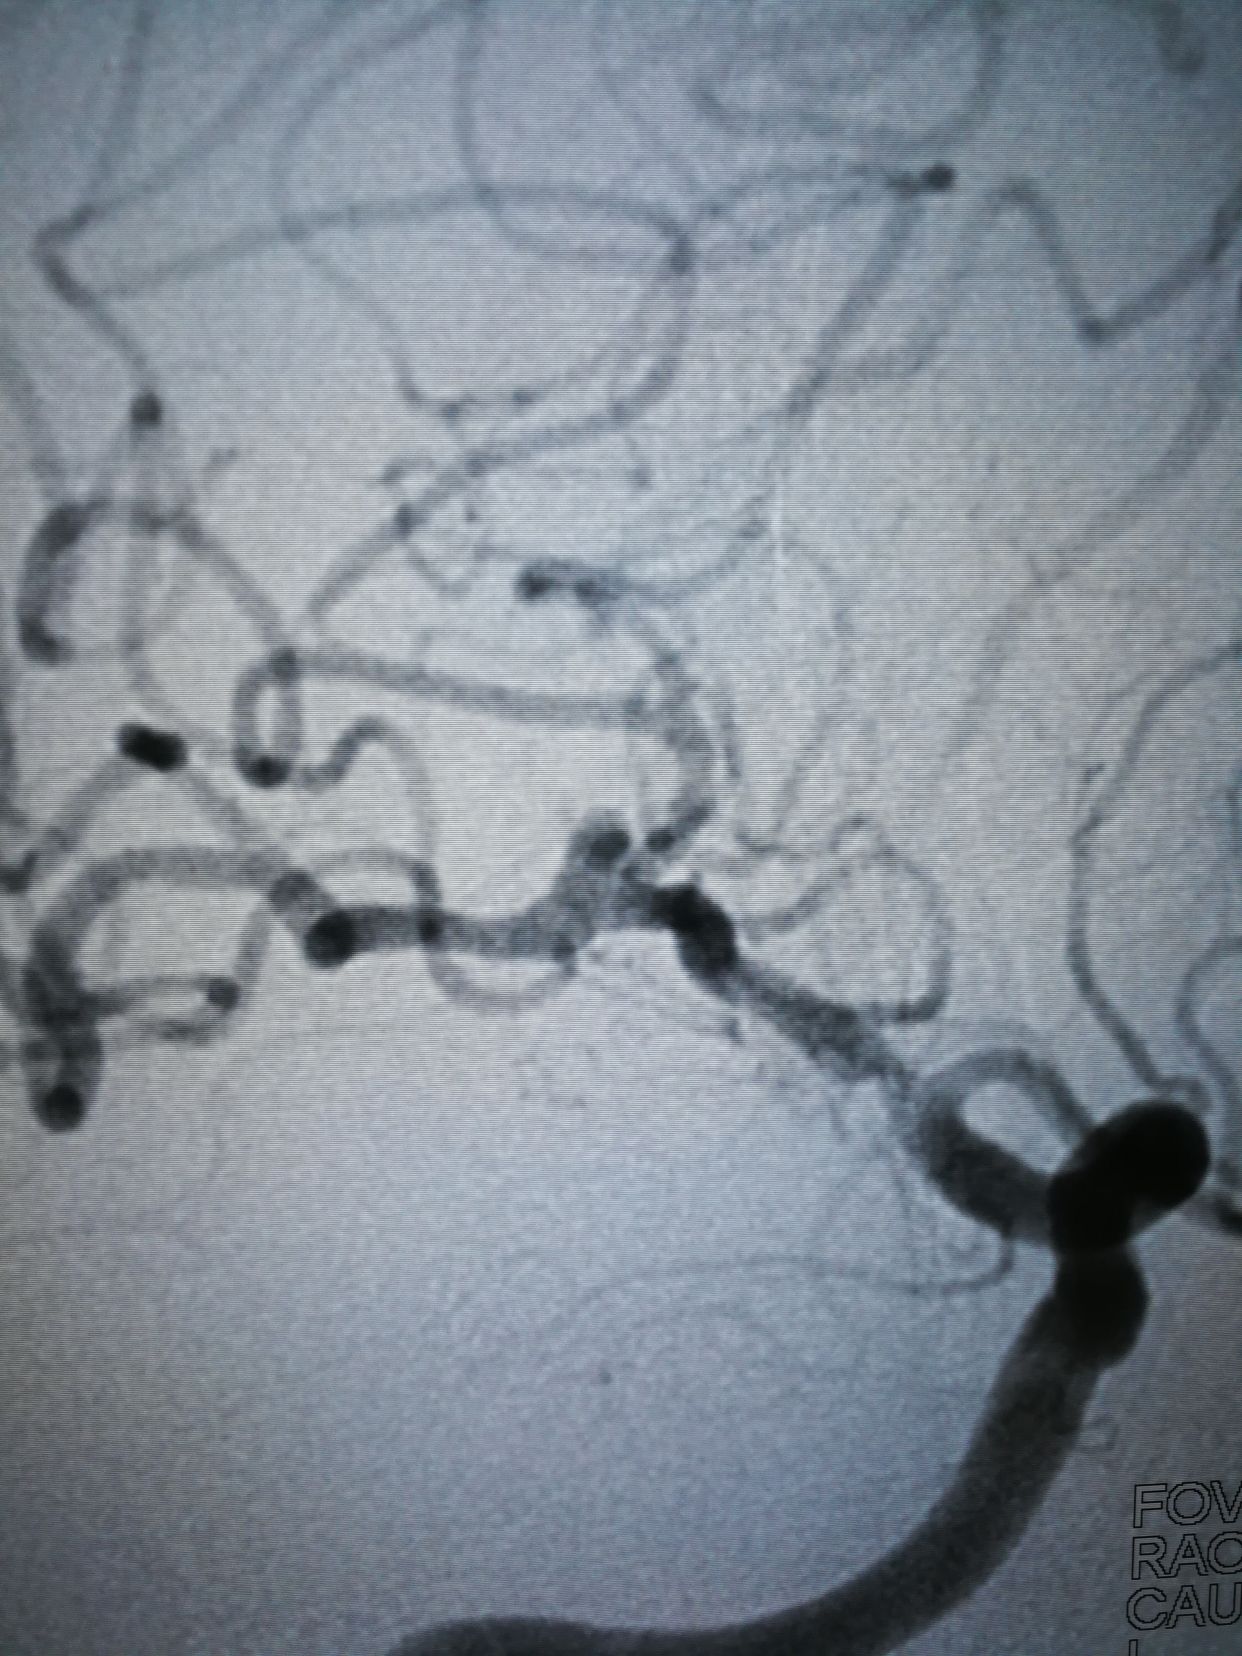

lvis25-17,支架打开很好,术后动脉瘤完全不显影。1个半小时结束战斗,收工回家。